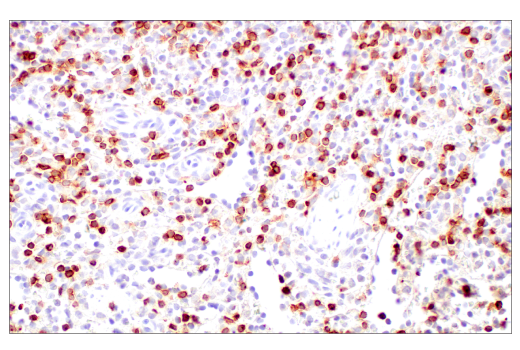

Immunohistochemical analysis of paraffin-embedded human T-cell lymphoma using CD2 (D6V9F) Rabbit mAb.

Immunohistochemistry Image 6: CD2 (D6V9F) Rabbit Monoclonal Antibody